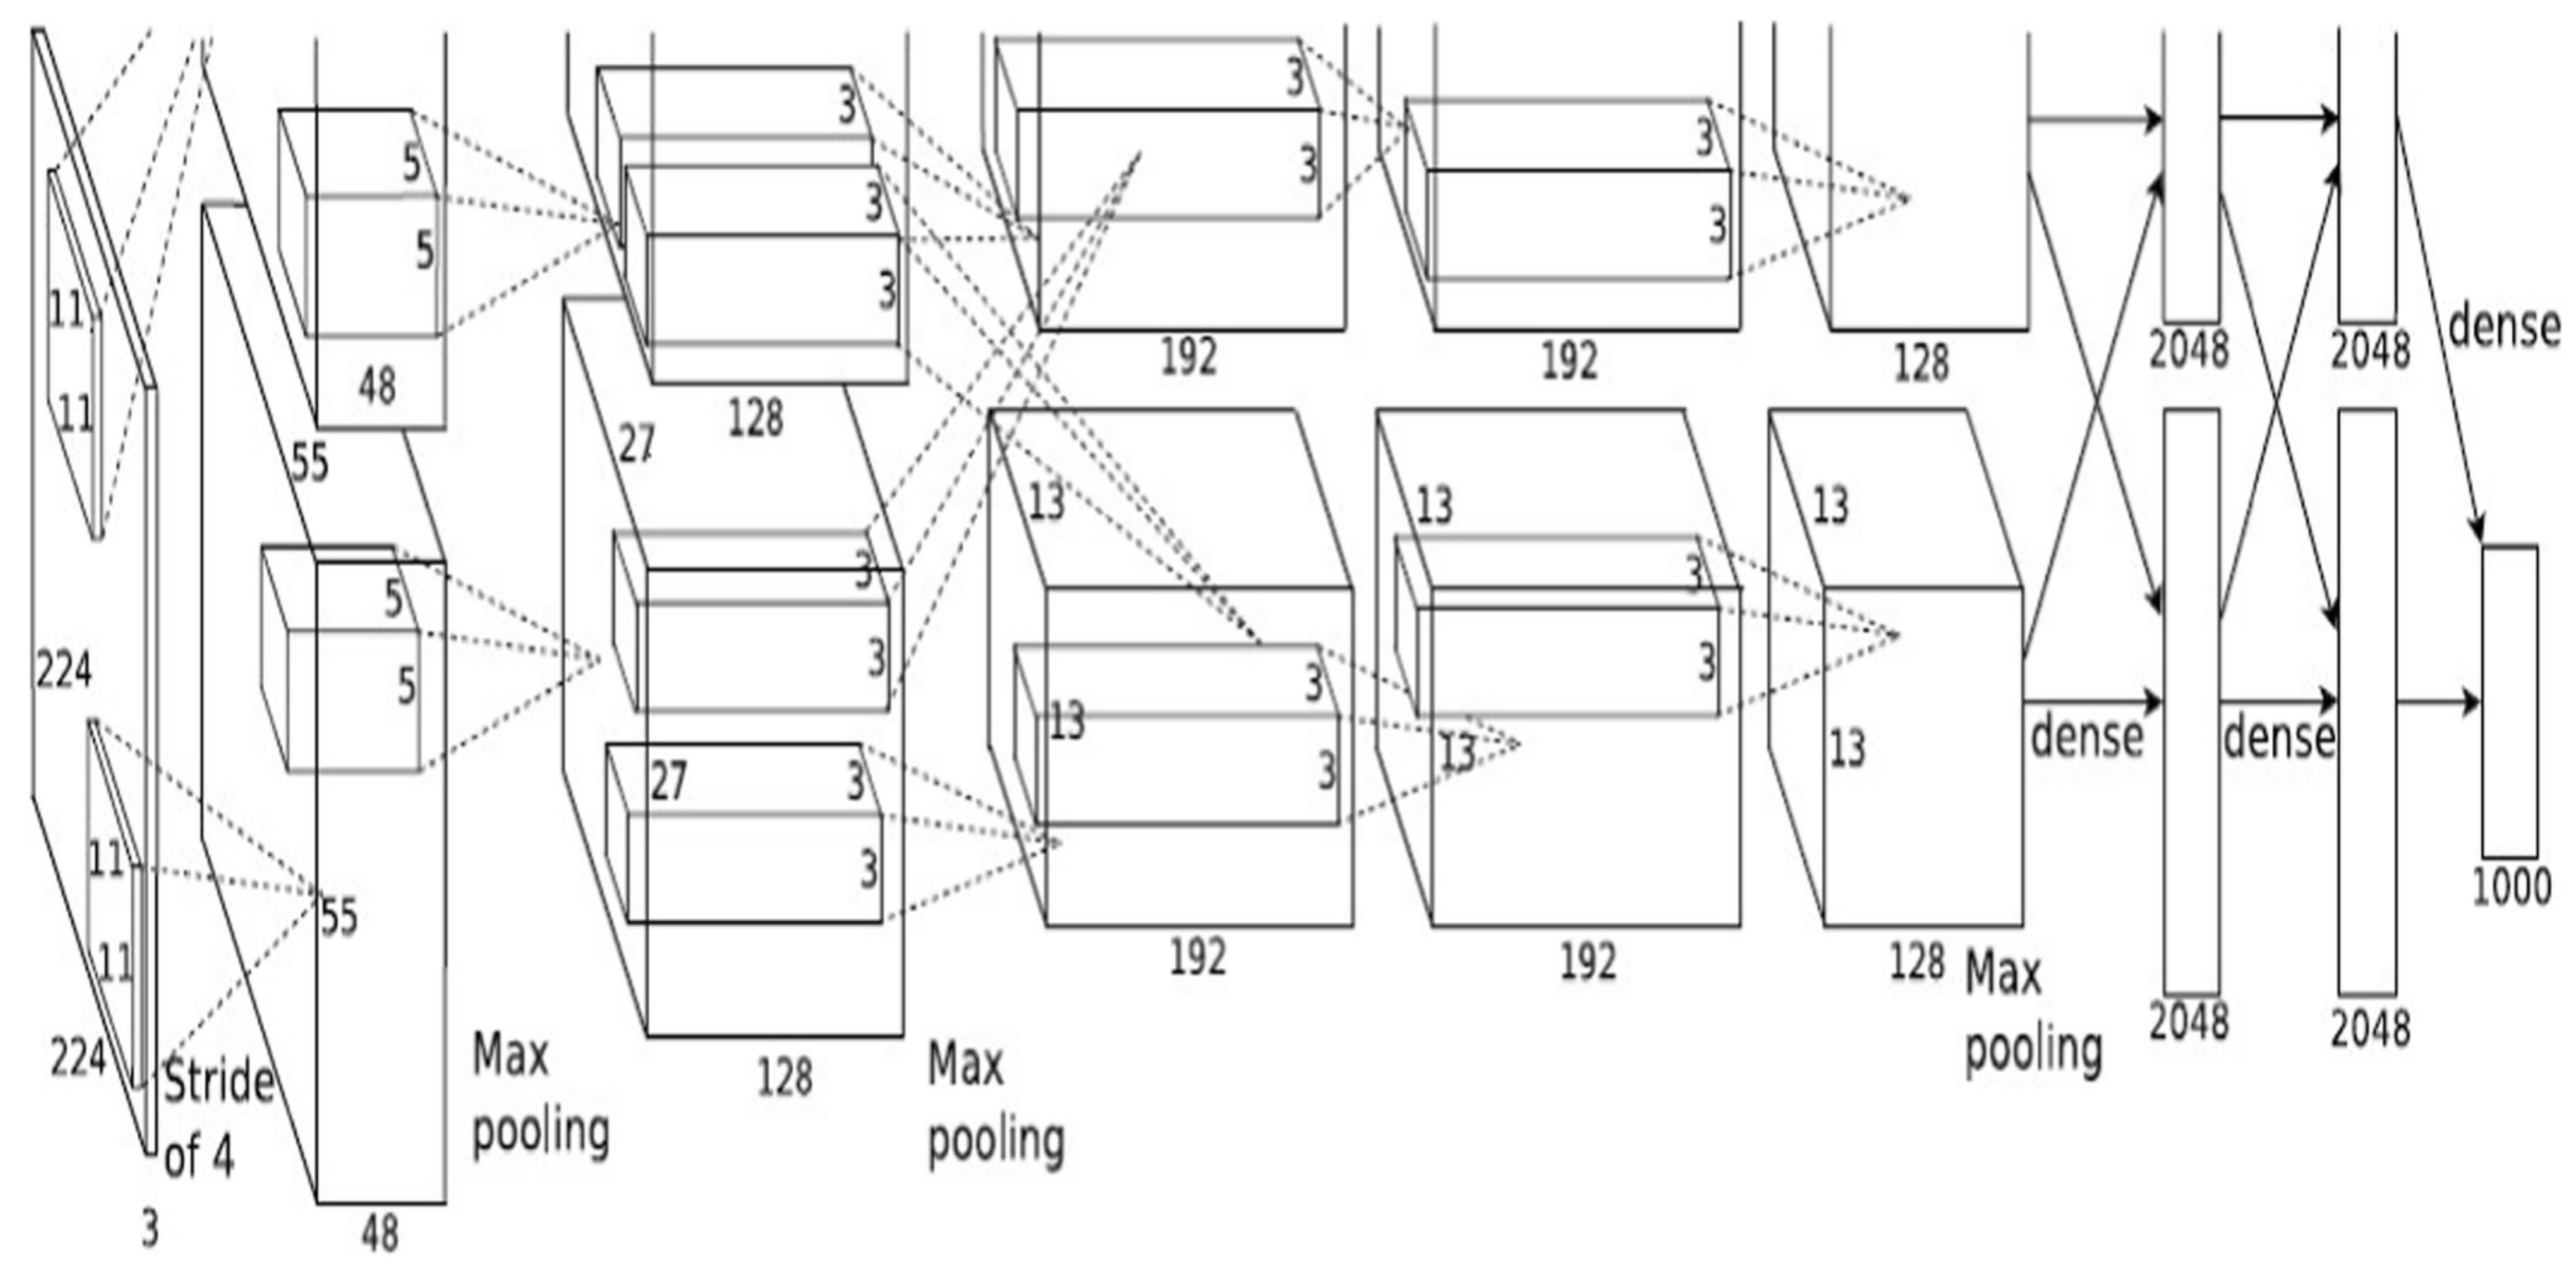

2.1. Deep Neural Networks

2.2.2. Feature Extraction

- Krizhevsky, A.; Sutskever, I.; Hinton, G. ImageNet Classification with Deep Convolutional Neural Networks. Proc. Neural Inf. Process. Syst. (NIPS) 2012, 1, 1097–1105. [Google Scholar] [CrossRef]